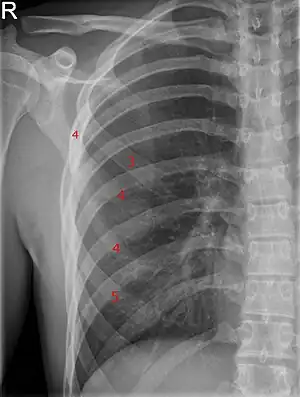

![]() | |

| Bifid rib at the right side seen on chest radiograph. The fourth rib splits in two towards the sternal end. | |